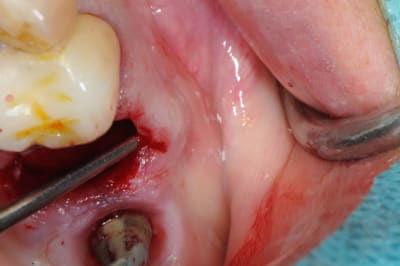

je poursuis donc mon cas clinique si vous voulez bien.

1- curette en appuie sur la face vestibulaire montrant la destruction osseuse.

2- lambeau pleine épaisseur en palatin pour aller chercher un bout de conjonctif qui soit pédiculé.

3 je décole à partit des rebords de la déhiscence osseuse et reste en contacte permanent avec la corticale osseuse tout en décollant la gencive (elle est soulevé donc)

4- comblement avec de la poudre de perlin-pin-pin

( désolé je suis pas au cabinet et je sais plus ce que j'ai mis dedans)

5-6- sutures du conjonctif pour obtenir l'étanchéité (enfin , on essaye)